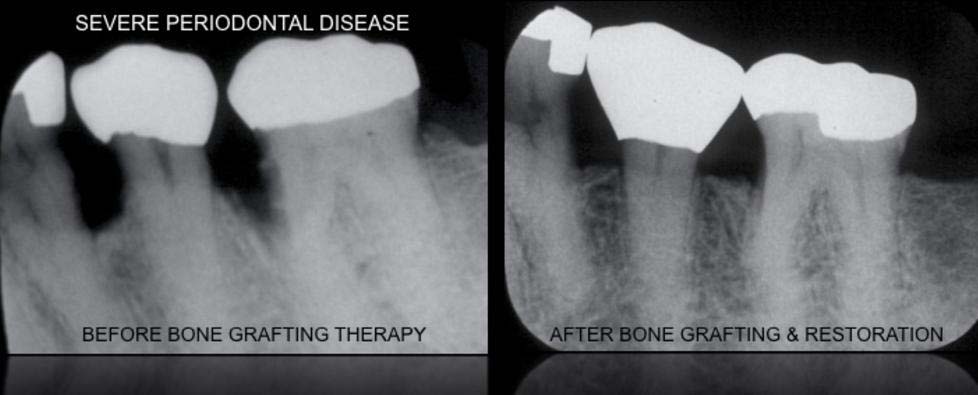

- NON-SURGICAL & SURGICAL THERAPY

- GUIDED BONE & TISSUE REGENERATION

- JAW RECONSTRUCTION ---> RIDGE AUGMENTATION